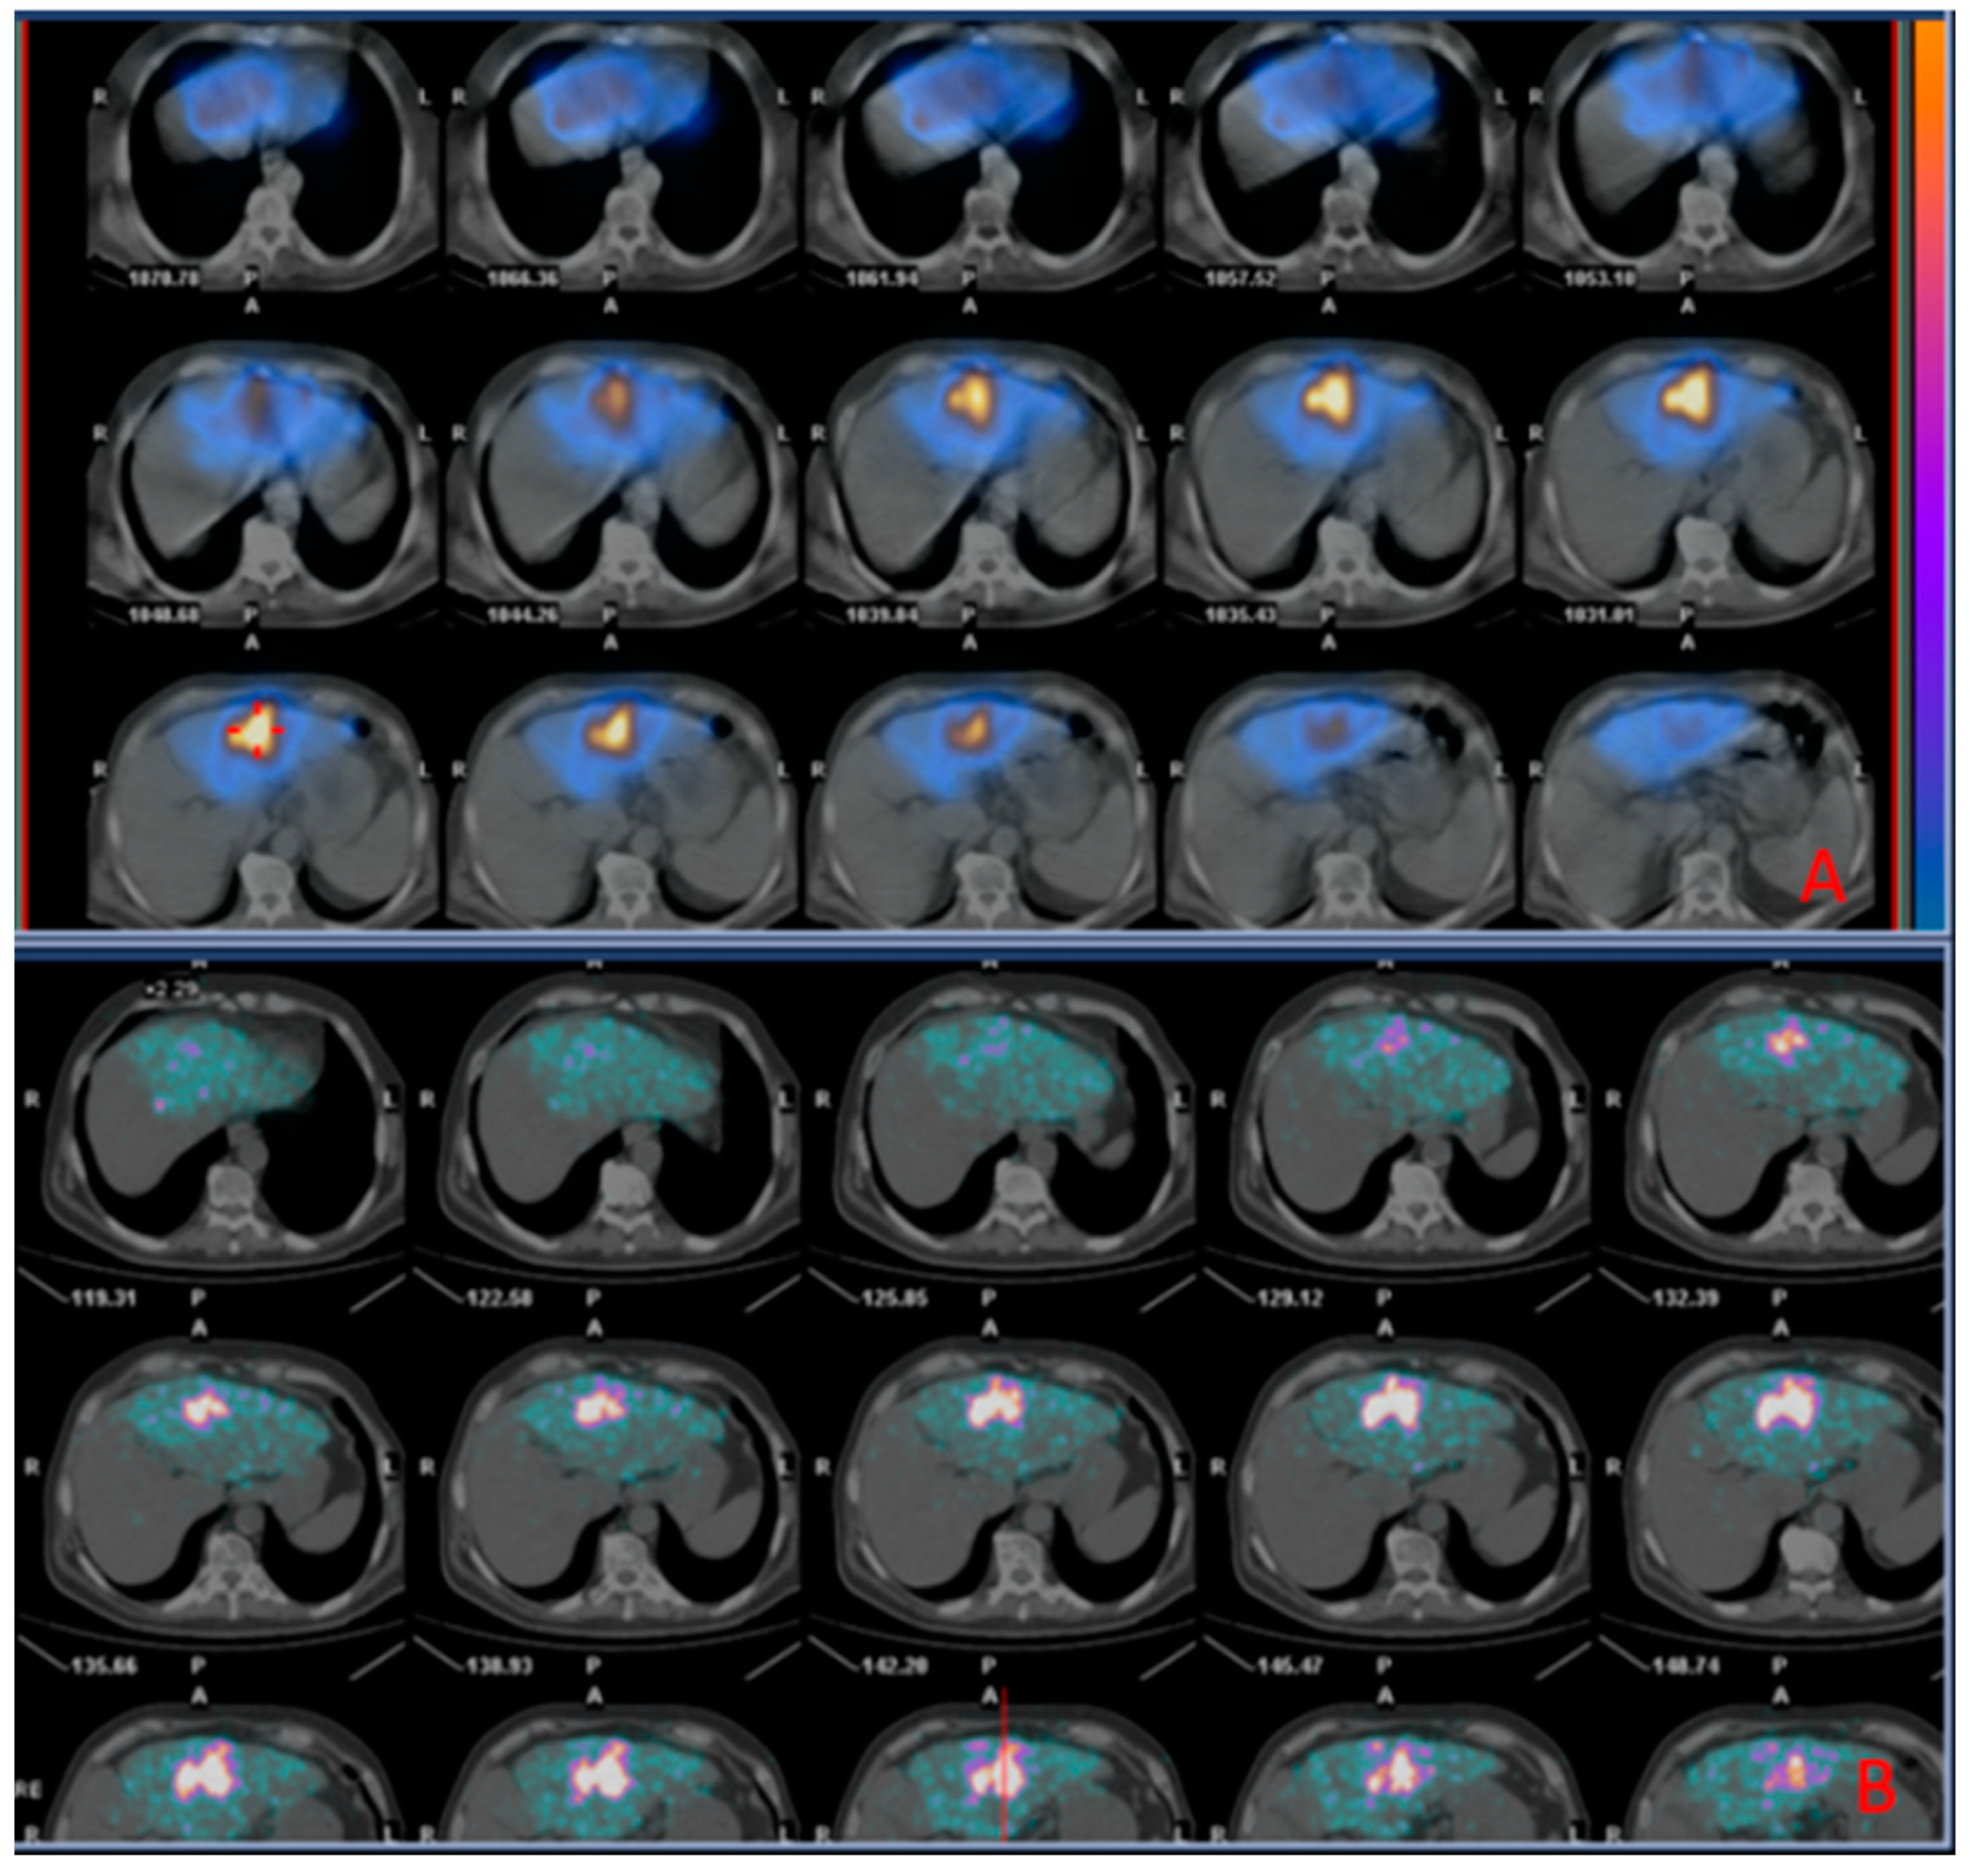

A representative case of a patient with CRC liver metastasis treated with TARE is shown in Figure 4.

Figure 4. Images of a patient undergoing radioembolization of a hepatic metastasis from colorectal cancer. (A) (Upper box): SPECT/CT images (diagnostic phase) 2 h acquired after administration of 99mTc-MAA; (B) (Inferior box): PET/CT images (therapeutic phase) acquired 2 h after the administration of 90Y TheraSpheres, showing successful distribution of 90Y TheraSpheres matching that of 99mTc-MAA in the diagnostic phase.